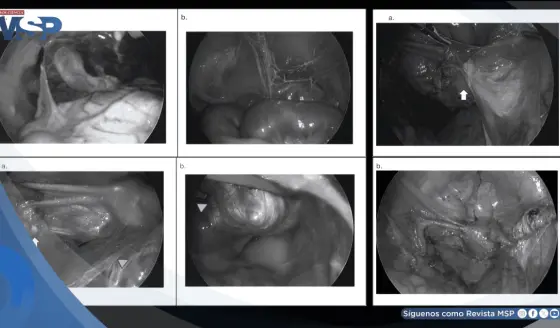

Tecnología robótica Da Vinci 5 para cirugía bariátrica: Precisión, seguridad y menor invasión